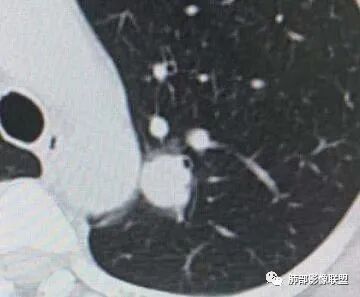

左肺上叶前段可见一磨玻璃结节,边界清,可见小叶间隔阻挡、毛刺 、胸膜牵拉,考虑微浸润腺癌。左肺上叶尖后段可见一实性结节影,边缘光整,光滑浅分叶,周围可见晕征,增强扫描明显延迟强化,可见血管贴边征,结节内未见气管及血管影,女性,考虑PSP

左肺上叶前段可见一磨玻璃结节,胸膜牵拉,考虑微浸润腺癌。左肺上叶尖后段可见一实性结节影,边缘光滑浅分叶,周围可见晕征,增强扫描明显延迟强化,可见血管贴边征,结节内未见气管及血管影,女性,考虑PSP。

左上肺近纵隔圆鼓结节,结节边界清楚,结节外周有境界清楚的磨玻璃,,有粗短毛刺和长毛刺,有胸膜凹陷,其内侧的支气管观察受限,建议薄层连续观察。综合考虑:腺癌

左肺上叶实性结节,光滑,晕,渐进持续强化,血管贴边,尾征,虑psp。另左肺上叶纵膈胸膜下磨玻璃结节收缩力强,胸膜牵拉,考虑腺癌,中带磨玻璃结节细节手机不好看,随访!

二.左肺上叶前段磨玻璃结节:

该结节较大,边界清楚,小叶间隔阻挡特征相当明显,微浸润腺癌的诊断几乎没有争议!

三.右肺上叶胸膜下结节及左肺上叶血管旁结节,尽管都是磨玻璃密度,但都比较小且边缘特征不明显,恶性征象未显露,处置并无特殊,定期复查!